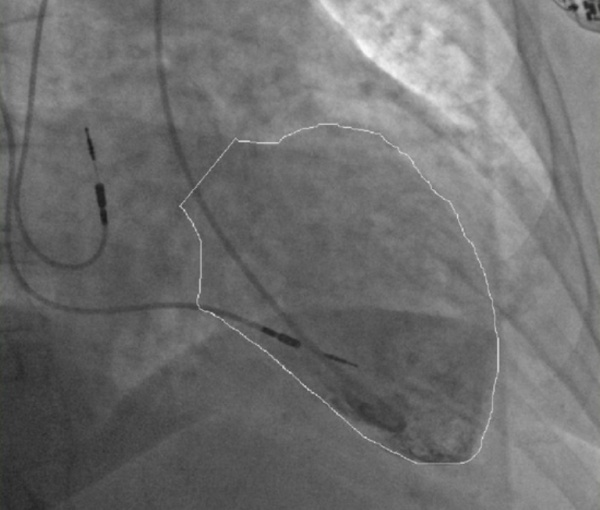

• Коронарная ангиография. Целью исследования в срочном порядке целесообразно исключить инфаркт миокарда. При кардиомиопатии неизмененные коронарные сосуды с сохраненным кровотоком визуализируются с помощью такоцубо. Для уточнения диагноза рекомендуется вентрикулография левого желудочка.

Вентрикулографии. Типичная для такоцубо кардиомиопатия является формой увеличения верхушки левого желудочка.